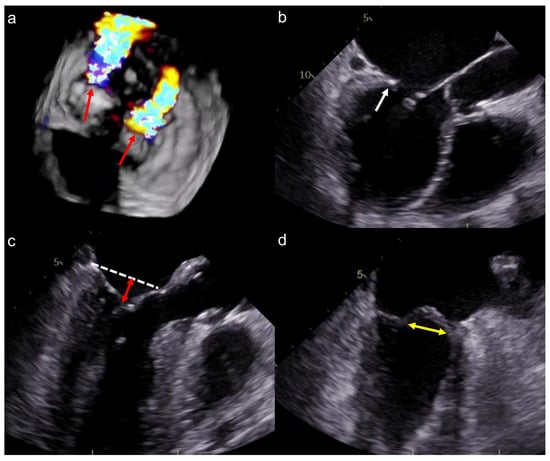

2.2. Echocardiographic Assessment

2.3. Computed Tomographic (CT) Assessment